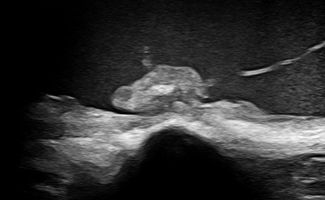

Elbow Ultrasound provides comprehensive imaging of various structures in the region, allowing the identification of pathologic conditions in the joint, bursae, tendons, ligaments, nerves, and soft tissues of the elbow.

- Fluid collection in the elbow joint (i.e. hemarthrosis)

- Fluid collection in the bursa (i.e olecranon bursitis)